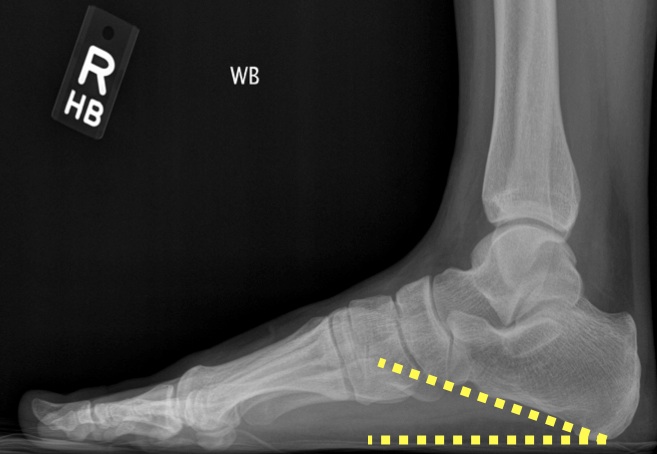

DEFINITION:

angle formed by the horizontal and a line from the base of heel & inferior cortex of calcaneus (figure 1). compare to pes planus (figure 2).

ABNORMAL:

if < 20 degrees then pes planus

if > 25 degrees then pes alta